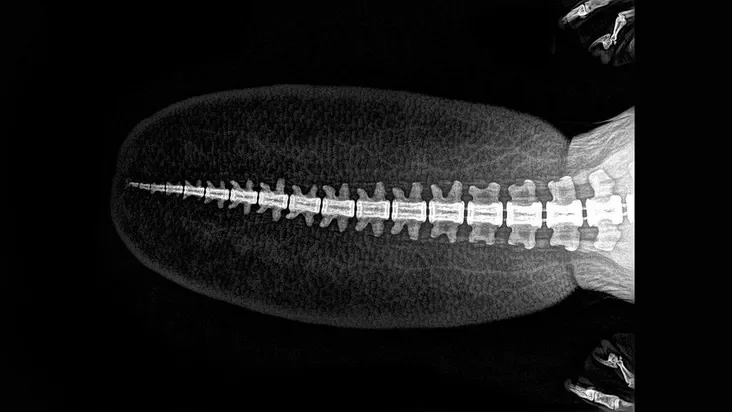

Зоопарк в американском штате Орегон опубликовал рентгеновские снимки своих животных. Их сделали во время медосмотра.

По словам представителей зоопарка, рентген — один из самых эффективных методов диагностики у животных. Кроме того, он позволяет минимизировать время анестезии при операциях.

Такие снимки редко обнародуют, поскольку их делают исключительно в исследовательских целях.

Хвост бобра.